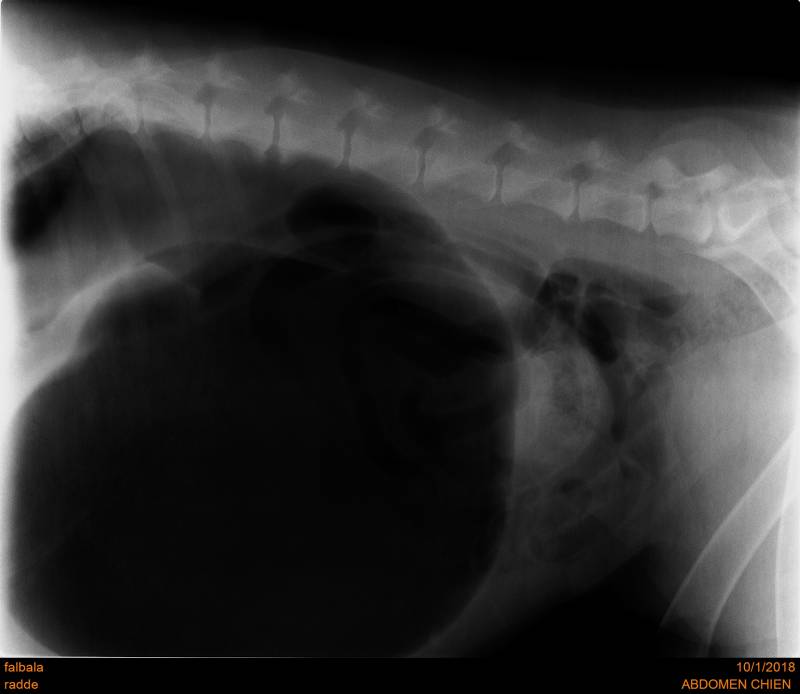

Le Syndrome Torsion Dilatation d'Estomac

Le syndrome dilatation torsion de l'estomac est l'urgence absolue du chien, de pronostic très réservé, elle doit être prise en charge le plus rapidement possible.